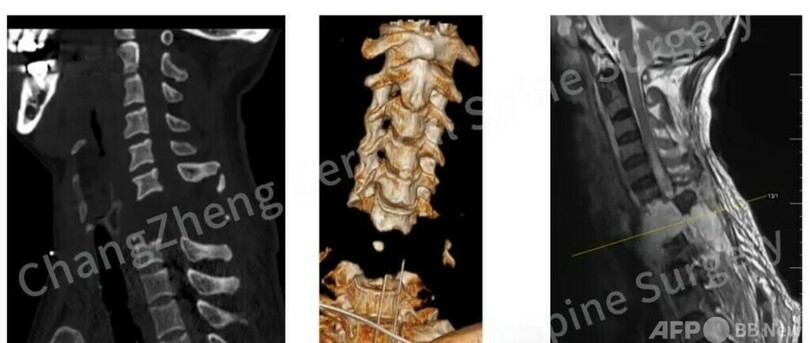

【8月22日 CGTN Japanese】中国東部の上海市にある上海長征病院の整骨チームがこのほど、多くの医学専門家と合同で3時間にわたる精密な手術を施し、ほとんど「首が胴体から切り離されたような状態」の頚椎骨折患者の頚椎固定手術に成功しました。

この患者はロボットアームに首を強打された衝撃のため、その場で高位脊髄損傷、心停止状態に陥りました。緊急心肺蘇生法により、かろうじて微弱なバイタルサインを取り戻しましたが、CTなどの検査により、頚椎に極めて広い範囲の脱臼が発生し、脊髄の重度損傷や、中枢神経の血管構造の断裂が認められました。

同チームは「頸椎固定プレート」という固定技術を革新的に応用し、従来の固定術に補助プレートを追加することで、再建された頚椎により強固な安定性を与えました。同技術がこのような極端な症例に応用されるのは初めてとのことです。